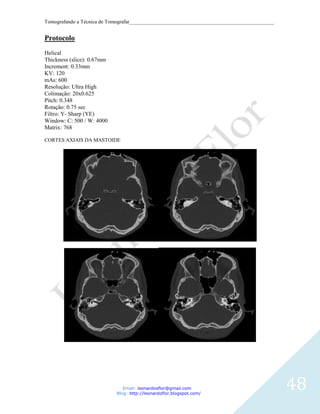

Protocolo

Helical

Thickness (slice): 0.67mm

Increment: 0.33mm

KV: 120

mAs: 600

Resolução: Ultra High

Colimação: 20x0.625

Pitch: 0.348

Rotação: 0.75 sec

Filtro: Y- Sharp (YE)

Window: C: 500 / W: 4000

Matrix: 768

CORTES AXIAIS DA MASTOIDE